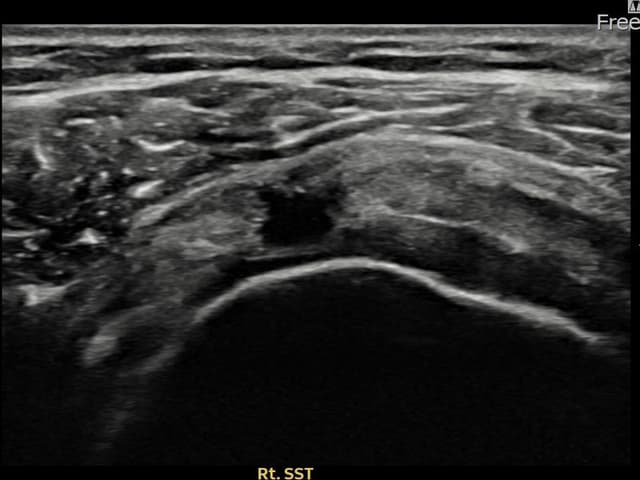

[経過期間: 23.09.01~23.11.03]

[縫縮術] 超音波検査にて右 棘上筋腱 滑液包面側部分断裂(8mm × 4mm (腱厚の約35%欠損))を確認。縫縮術施行後、腱の連続性が回復し、日常生活に復帰されました。